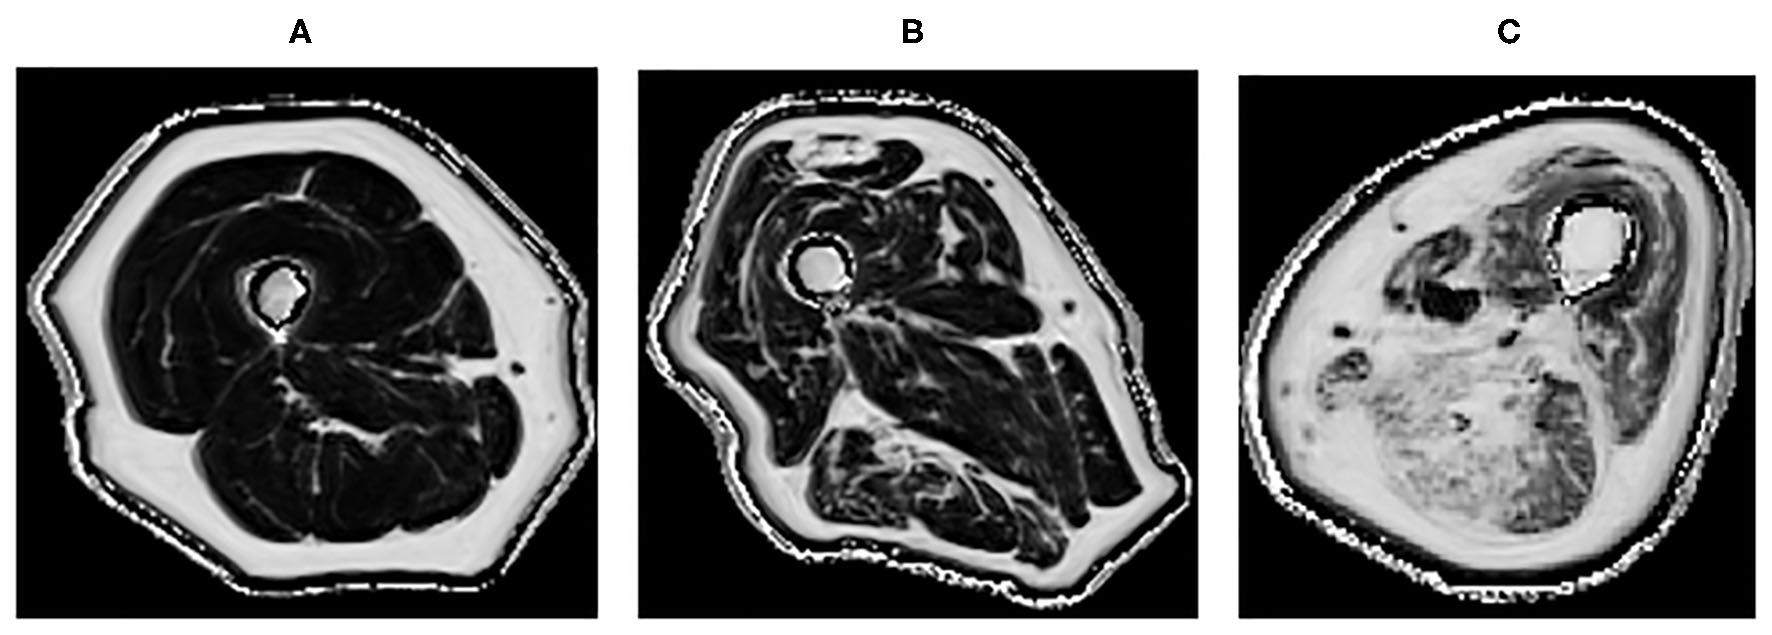

Quantitative MRI, which allows further characterization of the muscle structure at a microscopic level, can provide a more precise description of muscle pathology (55, 73, 79). It could potentially be used in longitudinal monitoring of disease (80). It has been demonstrated that T2 and fat fraction increase in myositis patients (Figure 2), demonstrating that MRI is sensitive enough to quantitatively detect muscle edema (55, 81) and myosteatosis (82). These measures could be used to more accurately guide muscle biopsies. This may be of greater importance in patients with low grade inflammation, where there are subtle muscle changes that might go undetected by conventional MRI. DTI measurements are sensitive to subtle changes in the muscle, and have been used to detect differences in muscle due to diseases including myositis (83). However, muscle DTI is far from standardized. The optimal methods and parameters for performing diffusion in muscle have not been established and larger studies are necessary to establish whether diffusion will be a useful tool for monitoring muscle disease in clinical practice.

Figure 2. Quantitative MRI fat fraction measurement in the quadriceps and hamstrings, respectively in the thigh in (A) 45-years-old healthy female with a fat fraction of 1.9 and 2.7%, respectively, (B) 83-years-old healthy male presenting with fatty infiltration associated with healthy aging with a fat fraction of 9.6 and 13.4%, respectively, (C) 60-years-old male with active myositis presenting with fatty infiltration with a fat fraction of 19.6 and 28.5%, respectively.